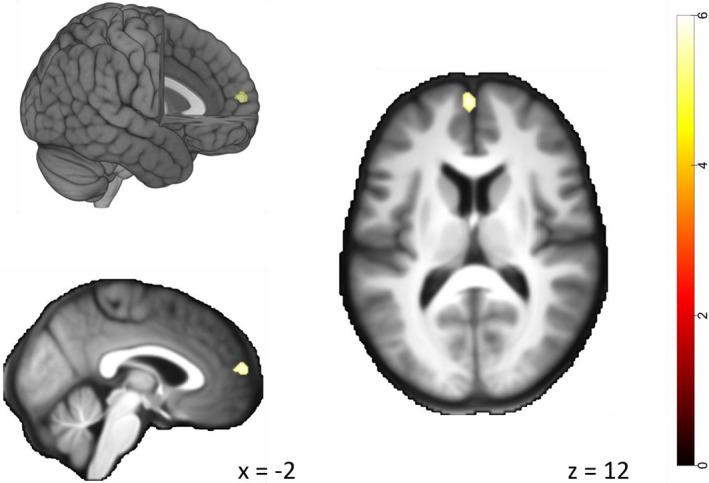

Our fMRI results show that people with TLE exhibited reduced response differences between fearful and neutral expressions displayed by humans in the right amygdala and the left superior temporal sulcus (STS). Further, TLE was associated with reduced response differences between human and avatar fearful expressions in the dorsal pathway of the face perception network (STS and inferior frontal gyrus) as well as in the medial prefrontal cortex.

我们的fMRI结果显示,TLE患者在右侧杏仁核和左侧颞上沟(STS)对人类展示的恐惧和中性表情之间的反应差异减小。此外,TLE与面部感知网络(STS和额下回)的背侧通路以及内侧前额叶皮质中人类和虚拟化身恐惧表情之间的反应差异减小有关。